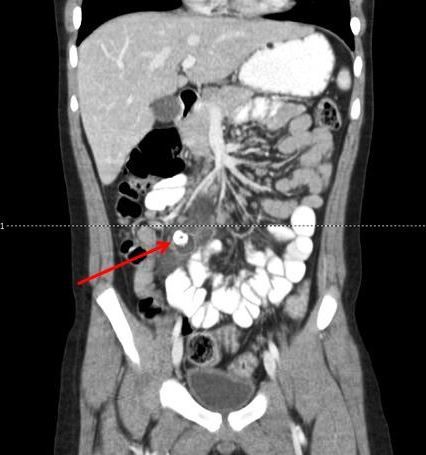

CT scan of the abdomen with contrast showed a 1.1-cm calcified density in the right lower quadrant and an adjacent 1.8 x 1.8-cm fluid collection (Figures 1, 2). The patient underwent exploratory laparotomy the next day and was found to have an appendicolith embedded below the mesentery of the terminal ileum with adjacent abscess; no appendiceal stump was present. A diagnosis of retained appendicolith with abscess formation was made, and the abscess and nidus were removed. The patient rapidly improved without complication and was discharged 1 week following surgery.